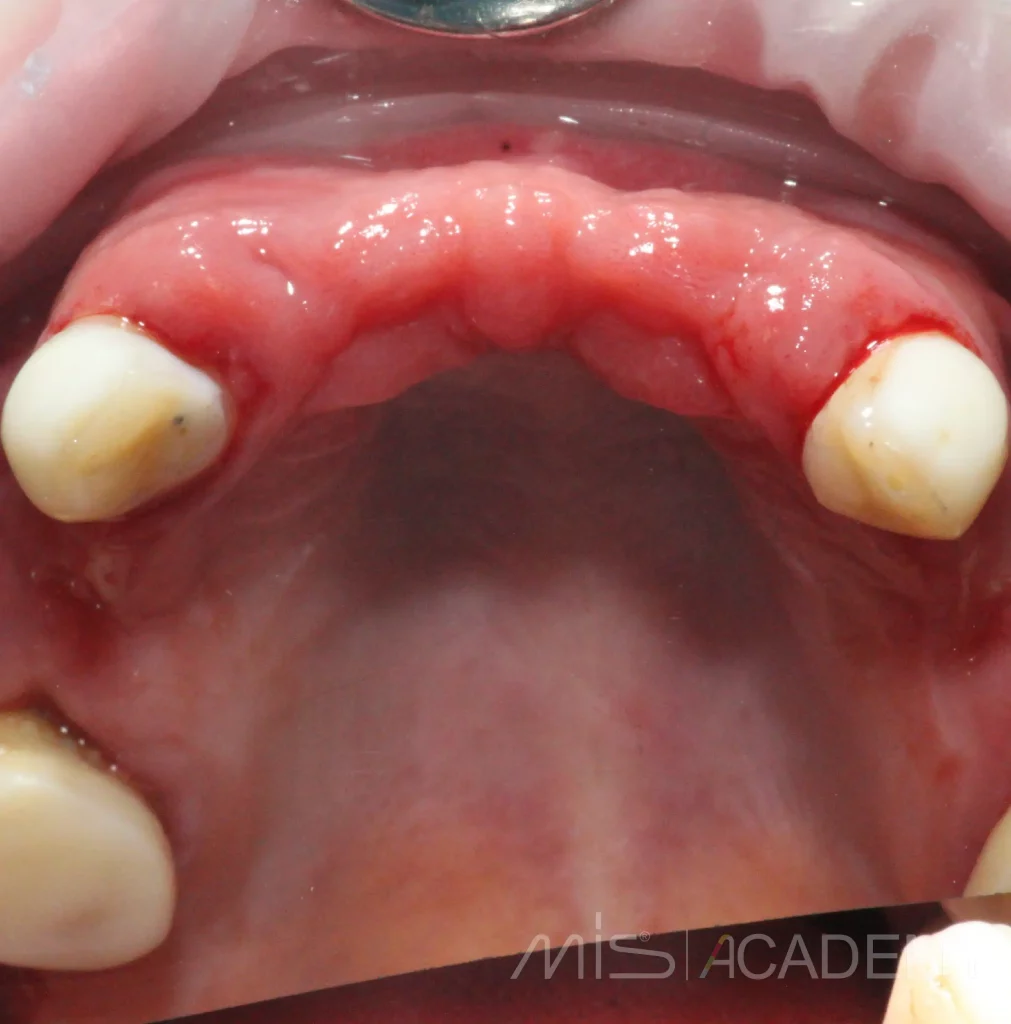

Клинический случай НКР верх фронт и последующие АО4 верх-низ.

На сегодняшний день возможно реализовал бы всё без НКР и возможно даже в FP1 (или аутоламинами, сократили бы сроки), но есть моменты по мягким тканям + вернусь ещё на устранение рецессии в области MU 24.